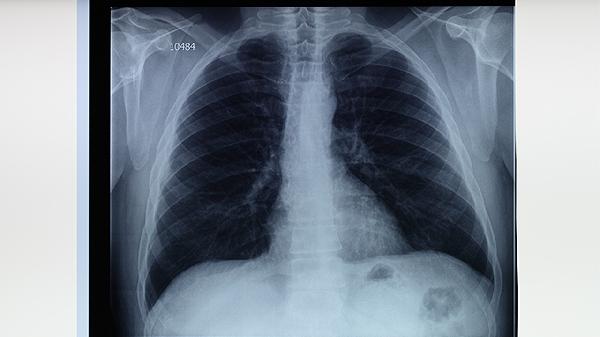

肺结核家庭的保健措施主要有隔离防护、环境消毒、营养支持、心理疏导、定期复查等。肺结核是由结核分枝杆菌引起的慢性传染病,家庭护理需兼顾治疗与预防传播。

严格遵医嘱完成6-8个月抗结核治疗,按时复查胸部CT和痰涂片。家属需监测患者用药不良反应,如出现视力模糊、关节痛等症状及时就医。密切接触者应进行结核菌素试验筛查。